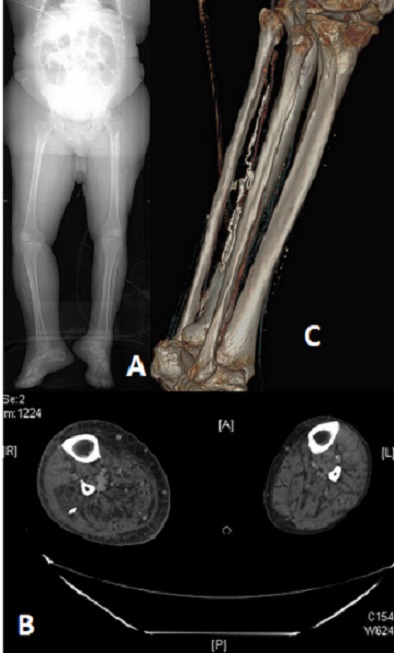

Il s'agit d'un patient de peau noir admis au service des urgences, pour une dermohypodermite du membre inferieur droit. Le traitement initial à base d'amoxilline protéger n'a pas donné de résultat efficace. L'aggravation clinique nous a poussé faire une TDM du membre, qui nous a montré un aspect de calcification filiforme. Des incisions de décharge, associée à une antibiothérapie de plus large spectre ont permit la résolution du problème. La filariose de Médine, est une maladie parasitaire causée par un nématode.ce ver appelé Dracunculus medinensis. Le nom de Dracunculus vient du latin «petit dragon». Il est présent dans des crustacés, les cyclopes, vivant dans l'eau stagnante. La femelle est le plus gros parasite qui puisse se loger dans les tissus humains, elle peut mesurer jusqu'à un mètre de long. Lorsqu'elle est fécondée, son corps n'est plus qu'un long sac s'ouvrant seulement par la bouche et occupé presque entièrement par l'utérus bourré d'embryons. Le métronidazole ou le thiabendazole (chez les adultes) est habituellement utilisé en complément de la méthode du bâton et facilite légèrement le processus d'extraction. Cependant, une étude a constaté que le traitement anthelminthique était associé à une migration anormale des vers, ayant pour résultat l'infection dans d'autres zones que les membres inférieurs. Par conséquent, de tels médicaments devraient être utilisés avec prudence. Le ver peut également être excisé chirurgicalement quand les équipements nécessaires sont disponibles. Chez notre patient la filariose était chronique, et elle a joué un support d'entretien de l'infection.